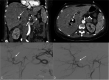

Figure 5. (A and B) Contrast tomography of the abdomen in coronal and axial views of the arterial phase with evidence of aneurysmal lesion (arrows) dependent on the right hepatic artery with signs of bleeding, (C) Fluoroscopy with angiographic evidence of an aneurysmal lesion of the right hepatic artery (arrow), and (D) subsequent successful embolization with coils (arrow)